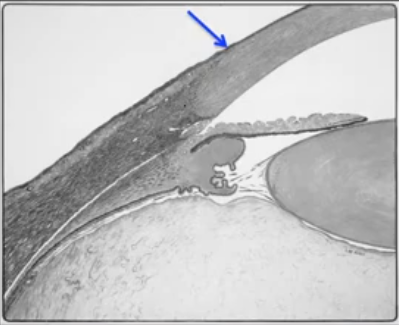

Usually autosomal dominant of PITX2 and FOXC1 --> These regulate neural crest migration → abnormal anterior segment development Axenfeld anomaly: Posterior embryotoxon + iris strands Rieger anomaly: Iris hypoplasia ± corectopia Rieger syndrome: Ocular features + systemic abnormalities

1. Posterior embryotoxon ⭐ (most common sign) Prominent anteriorly displaced Schwalbe’s line white peripheral corneal ring on slit lamp (Can also be present in normal individuals (~10–15%) 2. Iris strands to Schwalbe’s line bridging processes from iris to angle structures on gonioscopy 3. Iris hypoplasia ⭐ stromal thinning corectopia (eccentric pupil) polycoria (multiple pupil openings) 4. Angle dysgenesis abnormal trabecular meshwork anterior iris insertion peripheral anterior synechiae Leads to glaucoma risk. 5. Glaucoma ⭐ ≈50% of patients trabeculodysgenesis ± PAS Systemic features (Rieger syndrome) - Microdontia (missing small peg teeth) - maxillary hypoplasia - umbilical hernia - cardiac/hearing/skeletal/pituitary abnormalities